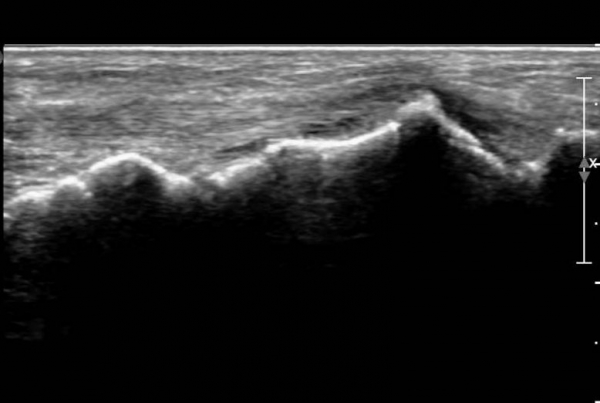

ŽÃËÀÚ¸¦ ¾à°£ ¹ß¹Ù´ÚÃøÀ¸·Î À̵¿ÇÏ´Ï ¼³Çü°ñ ºÎÂøºÎ°ÇÀÇ Àú¿¡ÄÚ º´º¯ÀÌ ¶Ñ·ÈÇÏ´Ù(»çÁø 3, 4).

Àü°æ°ñ°Ç Ⱦ´Ü¸é°Ë»ç¿¡¼­ Á»´õ ¹ß µîÃøÀ¸·Î À§Ä¡ÇÏ´Â Á¦1ÁßÁ·°ñºÎÂøºÎ °ÇÀº °í¿¡ÄÚ·Î Á¤»óÀûÀÎ ¾ç»óÀ¸·Î

°üÂûµÇ³ª Á»´õ ³»Ãø ¹Ù´ÚÃø¿¡ À§Ä¡ÇÏ´Â ¼³Çü°ñ ºÎÂøºÎ °ÇÀÇ Àú¿¡ÄÚ º´º¯ÀÌ °üÂûµÈ´Ù(»çÁø 5,  6).